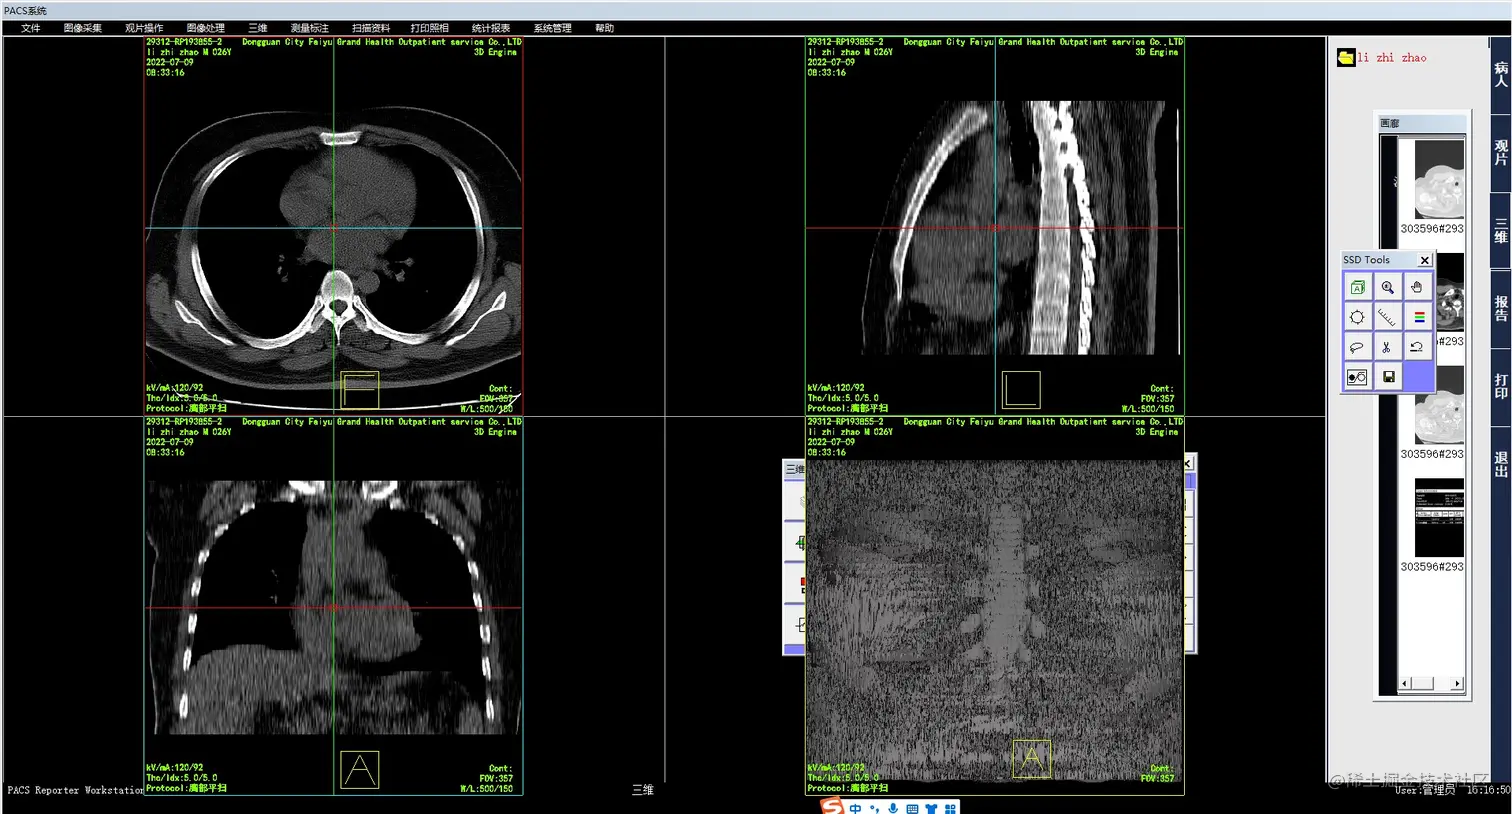

3.计算机阅片:影像医生可以通过系统的计算机阅片功能,快速、方便地浏览患者的影像资料,并进行快速的诊断和处理。系统将自动生成电子报告,并将报告发送给相应的医生和护士。

3.png